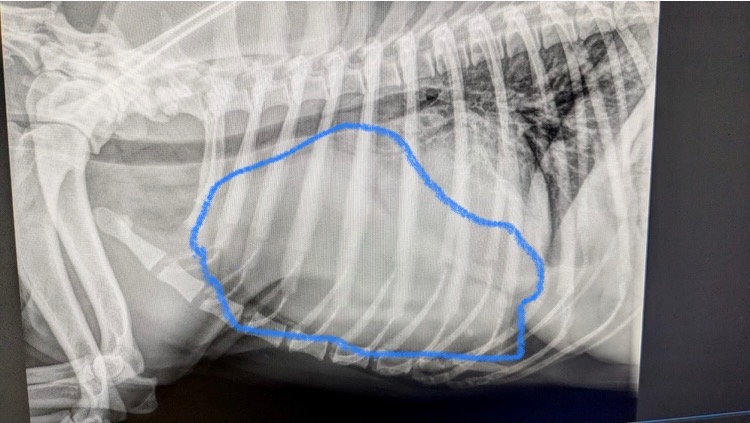

Hallo, ich bin Alex und sammle Geld für unseren Familienhund „Jeannie“ eine neunjährige Labrador Dame. Wir haben die letzten Wochen einiges hinter uns, durch Zufall kam heraus, das unsere Maus an einem riesigen Thymom leidet, das ist ein Tumor der im Brustkorb wächst und ziemlich selten ist. Er war riesig und drückte ihr Herz und Lunge zusammen, da war klar, dass „Jeannie“ nicht mehr viel Zeit blieb, auch wenn es ihr zu diesem Zeitpunkt noch recht gut ging.